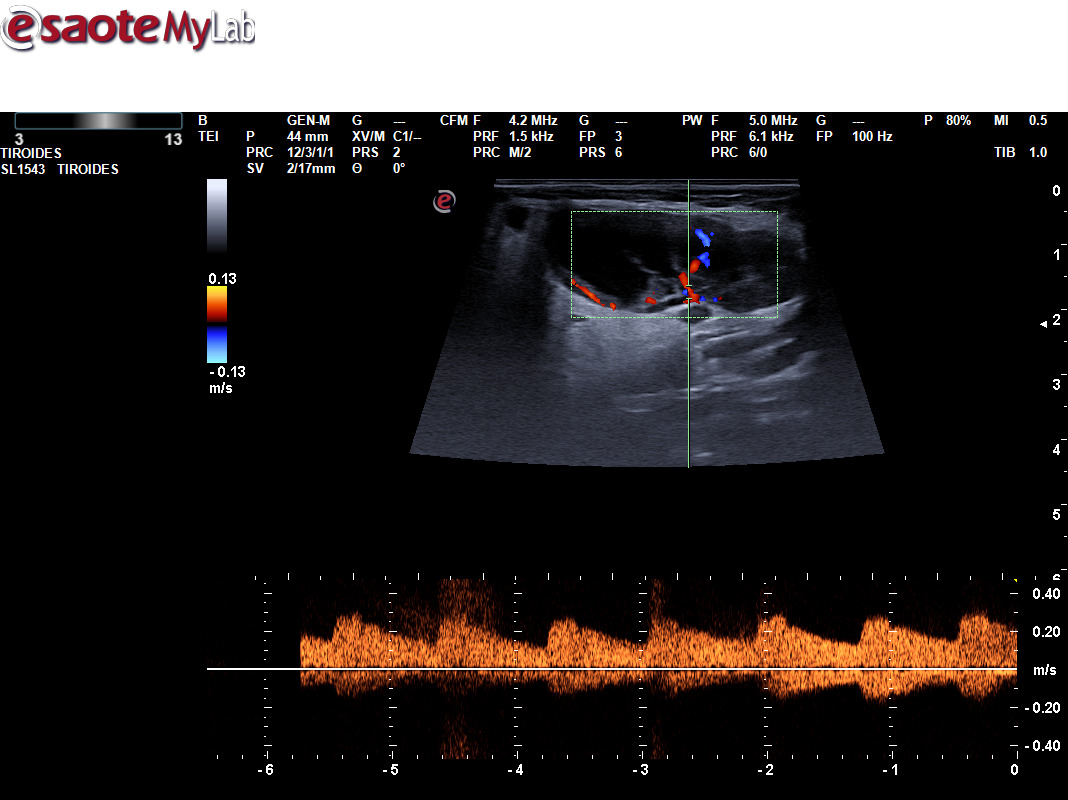

A través de distintos casos clínicos queremos valorar la importancia de la ecografía clínica en pacientes que consultan por la aparición de una masa cervical. Tras valorar a varios pacientes que han consultado por una masa cervical, hemos realizado una sesión clínica formativa sobre el aprendizaje de la ecografía cervical. Durante este periodo hemos podido diagnosticar diferentes patologías utilizando ecografía clínica y apoyándonos en otras pruebas complementarias, como un tumor de Merkel, un tumor de Warthin, una mononucleosis infecciosa, inflamación de un ganglio linfático por infección, un adenoma pleomorfo en glándula submandibular, malformación vascular, microlitiasis parotídeas, tuberculosis y un mieloma múltiple.

La ecografía ayuda a determinar las características de la masa, como su tamaño, forma y consistencia, lo que puede ayudarnos en la sospecha de patología maligna.

Permite distinguir entre diferentes tipos de tejidos, como quistes, ganglios linfáticos inflamados o tumores, lo que es crucial para un diagnóstico adecuado.